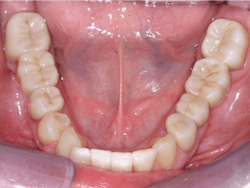

It has been estimated that about 90% of indirect restorations in the US are single crowns, and the majority of these single crowns are for posterior teeth. The phenomenal success of the original formulation of zirconia (3Y or Class 5 tetragonal zirconia) is now well proven. With the limitation of often less-than-desirable esthetic qualities, this material has become the most-used material for posterior crowns (figure 1).